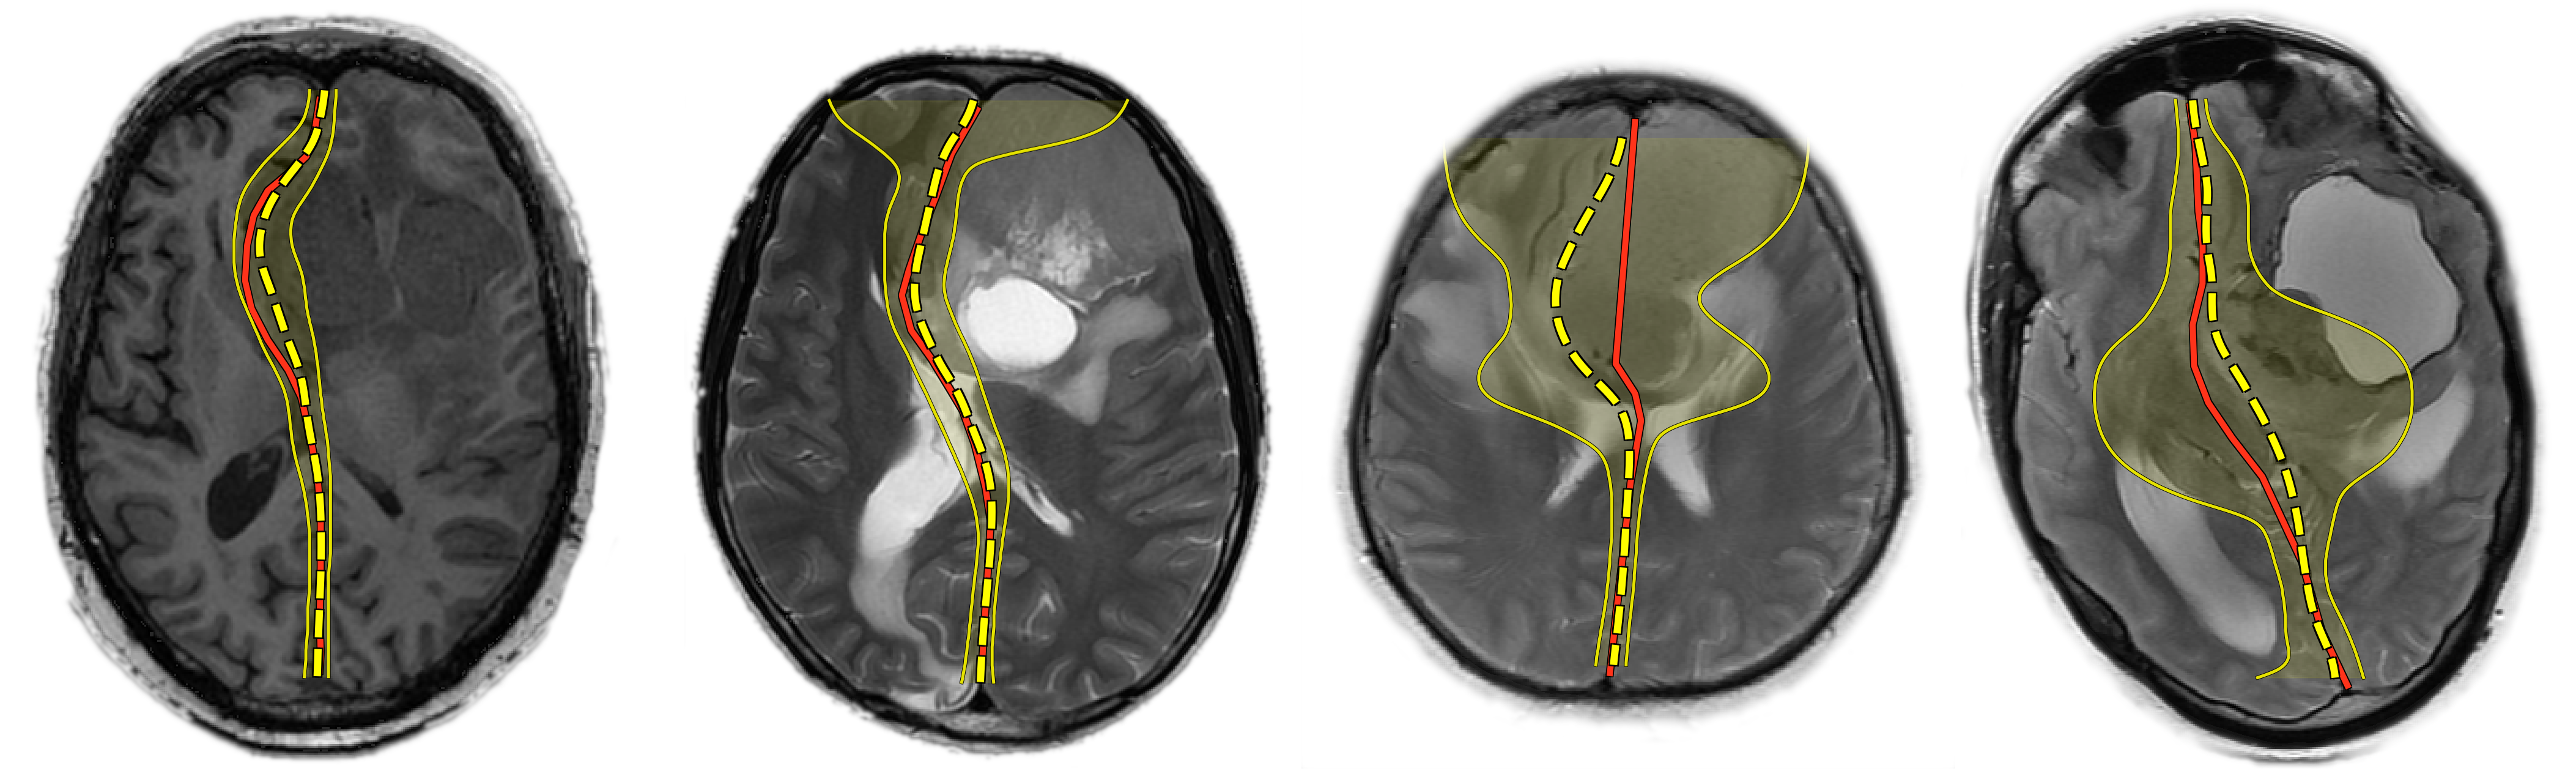

The brain midline can be viewed as a line on axial and coronal projections of diverse imaging modalities (Fig. 1, left). As the human brain is approximately symmetrical, the midline is straight in healthy subjects. However, various pathological conditions, such as traumatic brain injuries (TBI), stroke and brain tumors, may break this symmetry and lead to midline shift (MLS) [8].

Figure 1: Left: an axial slice from a MRI image with corresponding midline (red) and a hypothetical normal midline (blue, dashed). Center: the midline shift. Right: a dubious case with an ill-defined midline (red, dashed).

2 Problem

We define the midline on an axial slice as a vertical curve that separates the brain hemispheres (Fig. 1, left). The midline shift for an axial slice is then defined as the maximal distance between the midline (which might be deformed) and a hypothetical normal midline (Fig. 1, center). Finally, the midline shift for a whole brain is the maximal midline shift across all axial slices where the midline is present. The task is to determine, for a given brain image, the midline shift as well as the corresponding axial slice on which it is manifested.

It is worth noting that in some complicated cases even professional radiologists cannot confidently determine the localization of the midline (Fig. 1, right). Taking into account such dubious cases, it is also desirable that the method for MLS detection has a means of estimating its own confidence.

Refer to caption

Figure 4: Ground-truth (red) and predicted (yellow, dashed) midlines with their 95% confidence intervals for 2 random samples (left) and 2 typical examples from the set of cases with the largest errors (right).

Fig. 4 (right) shows several examples on which our method performs poorly. Our analysis of such examples suggests that the main source of errors are some really complicated cases that even professional radiologists have doubts with, e.g. images on which the tumor is located directly in the middle of the brain, or incorrect cases with an extracerebral tumor located in the medial longitudinal fissure, e.g. falx meningioma. Note how in the areas of greatest error the model’s uncertainty is much higher.